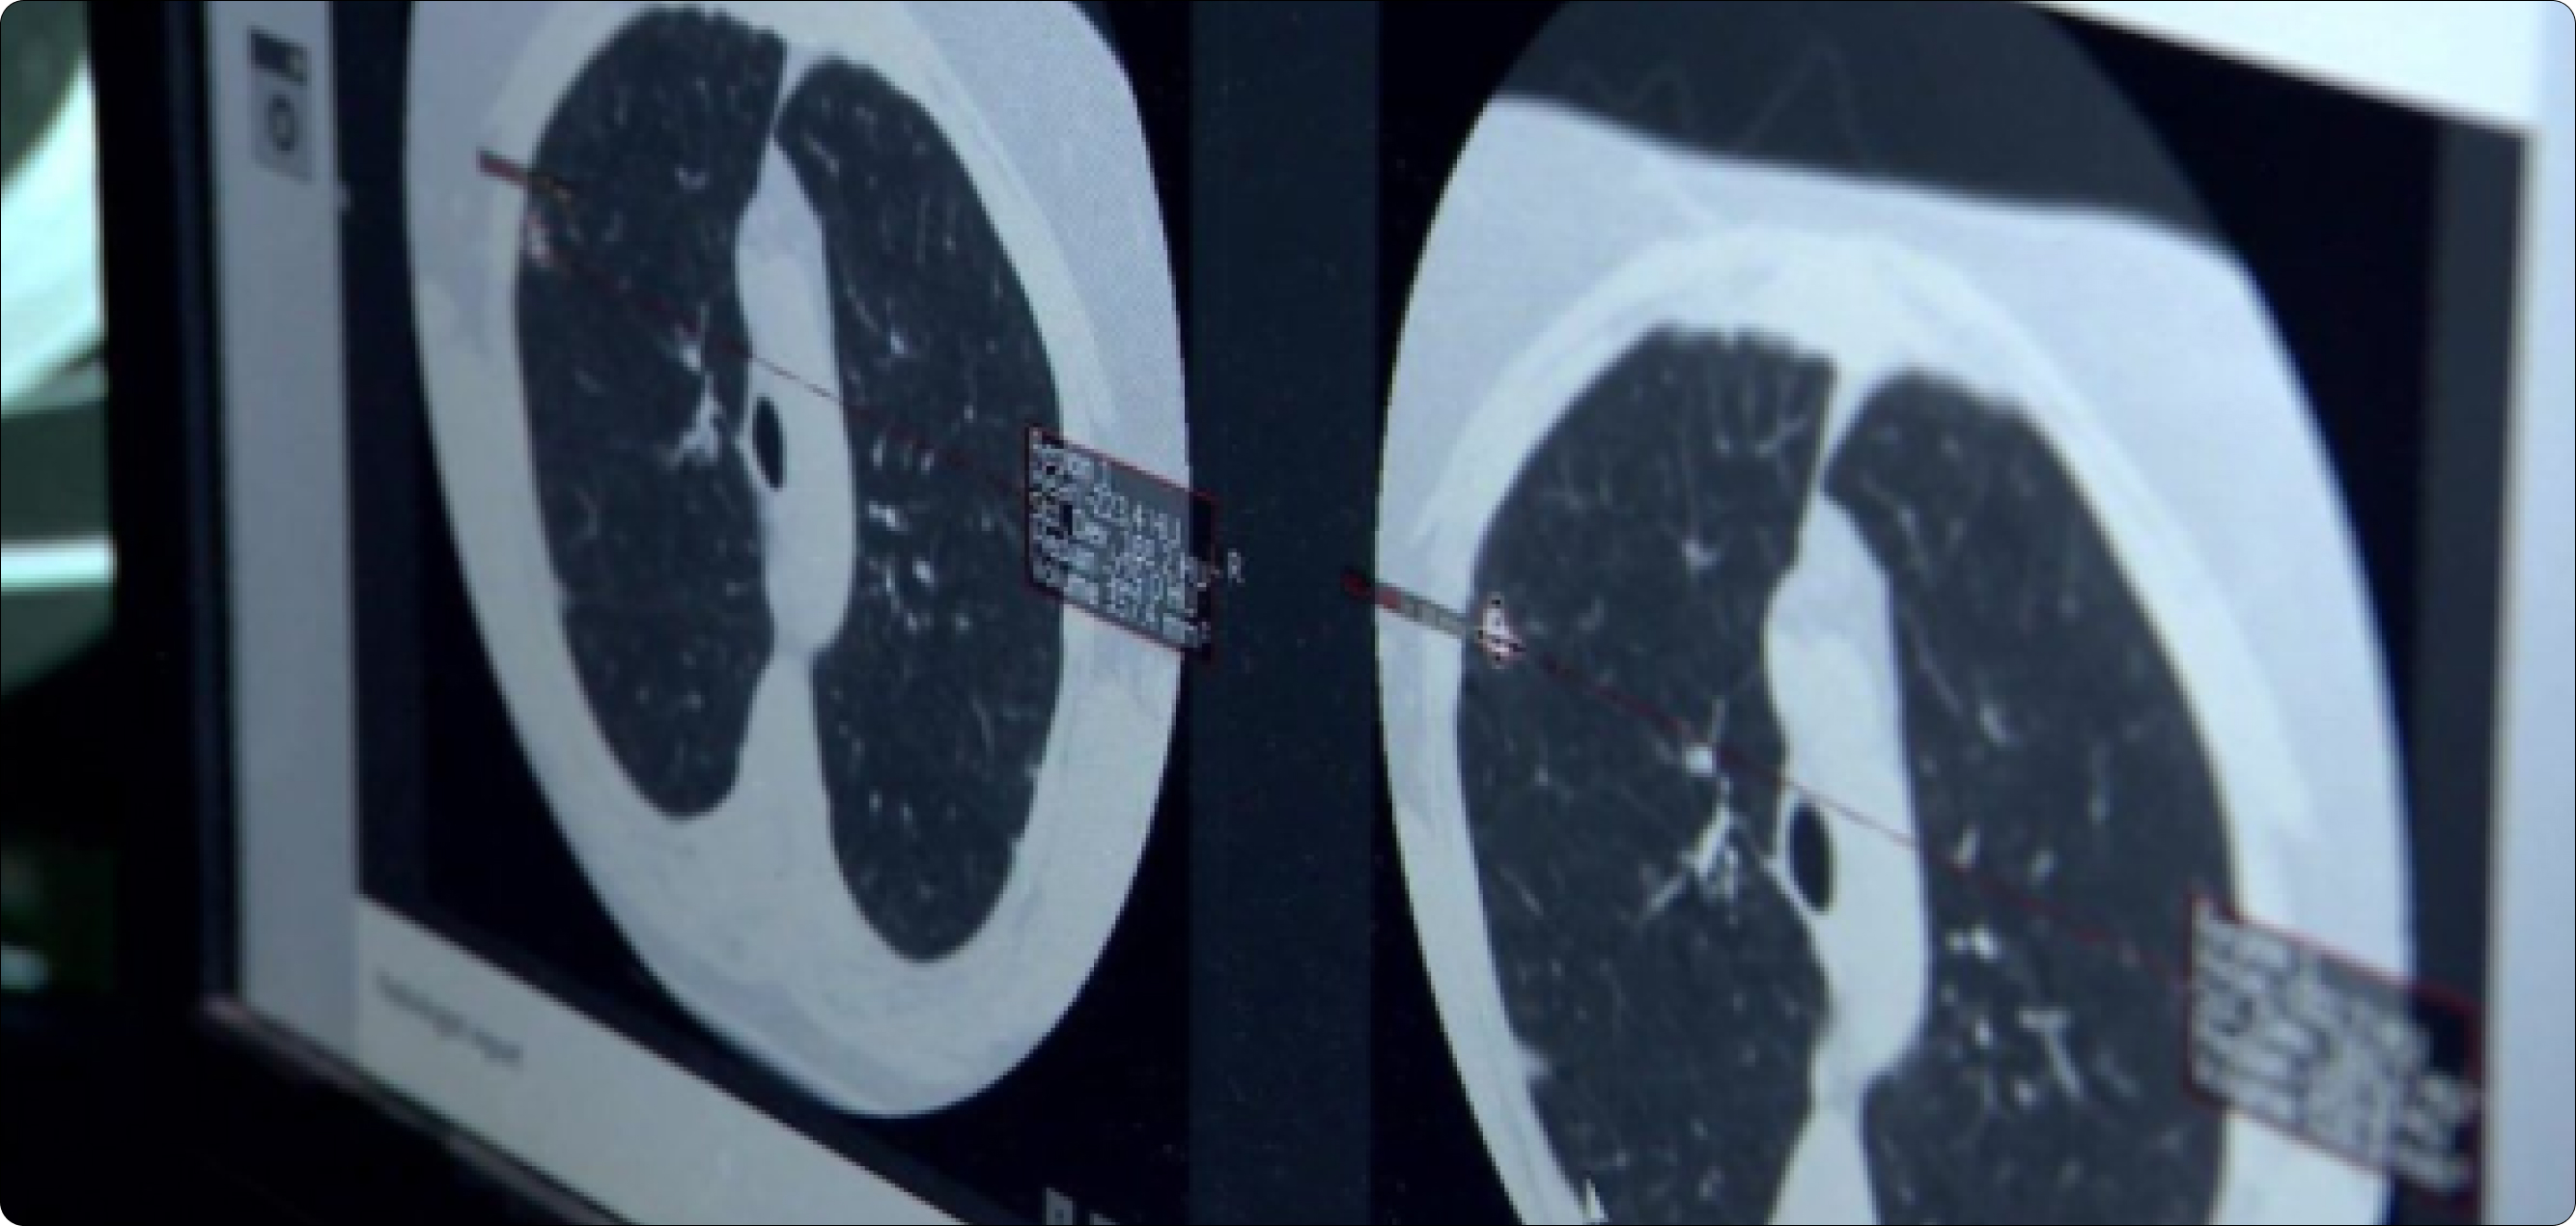

The potential benefits of artificial intelligence in medicine are actively being researched. The medical industry has a large amount of data that they may use to construct healthcare-related predictive models. In some diagnostic scenarios, AI has proven more effective than physicians. The lung cancer AI system below, for example, can provide a very early warning of the disease.